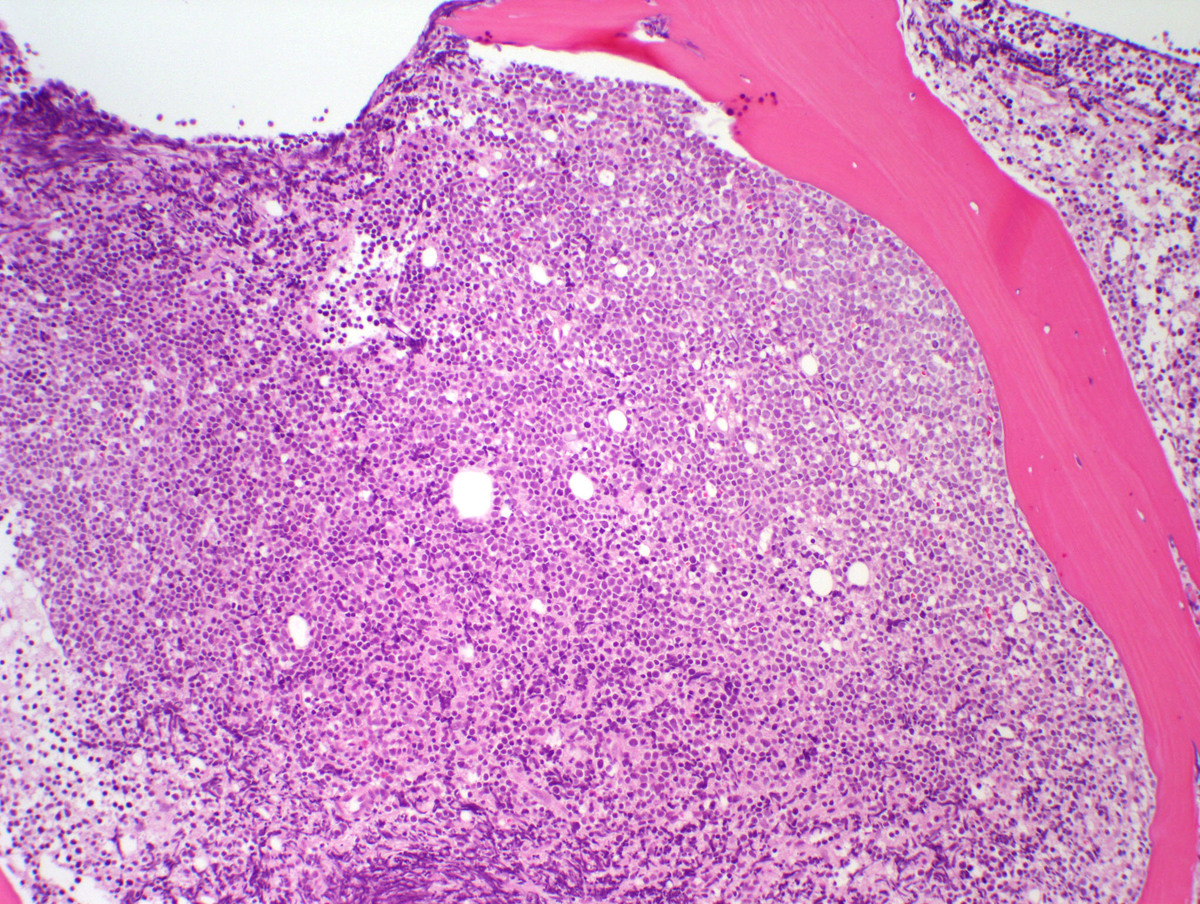

A bone marrow biopsy was markedly hyper-cellular (>95%) with near total replacement of the normal hematopoietic elements by sheets of monotonous immature cells. EBER (EBV) in situ hybridization was negative.IMMUNOHISTOCHEMISTRY AND FLOW CYTOMETRY

| Bone Marrow core 100x | ![]() |